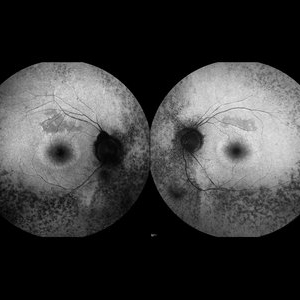

Retinitis Pigmentosa

Bilateral fundus autofluorescence images of retinitis pigmentosa.

Photographer: Olivia Rainey

Imaging device: Heidelberg Spectralis

Condition/keywords: 50 degrees, bilateral, fundus autofluorescence (FAF), hereditary retinal dystrophy, retinitis pigmentosa